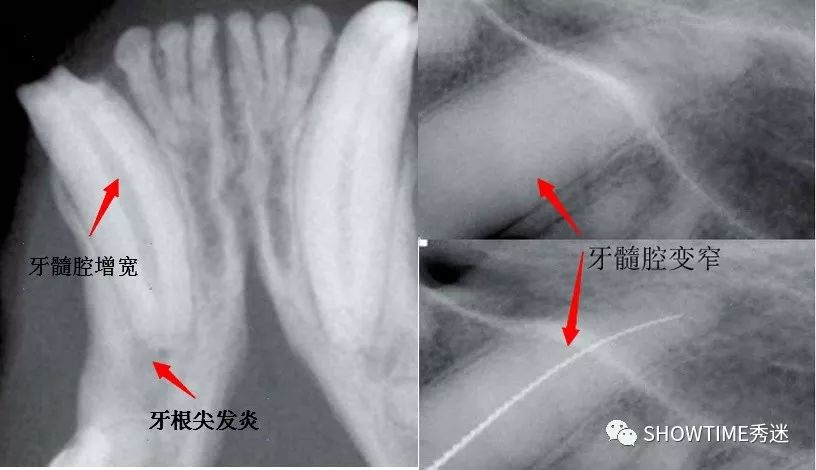

复杂齿折,是牙釉质和牙本质都被折断,暴露了牙髓腔。牙髓腔内的血管、神经、淋巴及结缔组织也就暴露在外,有时还会明显看到少量出血。因为口腔本身的潮湿开放的环境、细菌等病原体多等因素,发生复杂齿折后,处置不及时,非常容易发生牙髓感染。

如果进一步恶化,可能会导致很严重的疾病!例如深度的牙髓炎、牙根尖周炎甚至牙根周脓肿、牙槽骨炎、牙槽骨溶解……还因为牙髓神经对外界的刺激特别敏感,产生难以忍受的剧烈的疼痛,让毛孩子们痛苦不已。

牙髓炎的各种表现形式